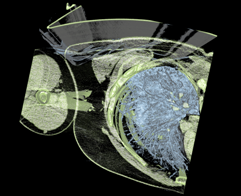

- A CT scan of the right upper thorax and arm of the same member of the SPECgpc committee, who has also released this data for use in SPECviewperf. The volume consists of 512x512x102 16-bit samples.

- Thorax CT, 2D transfer, ray-casting

- Thorax CT, 2D transfer, ray-casting, clipping plane